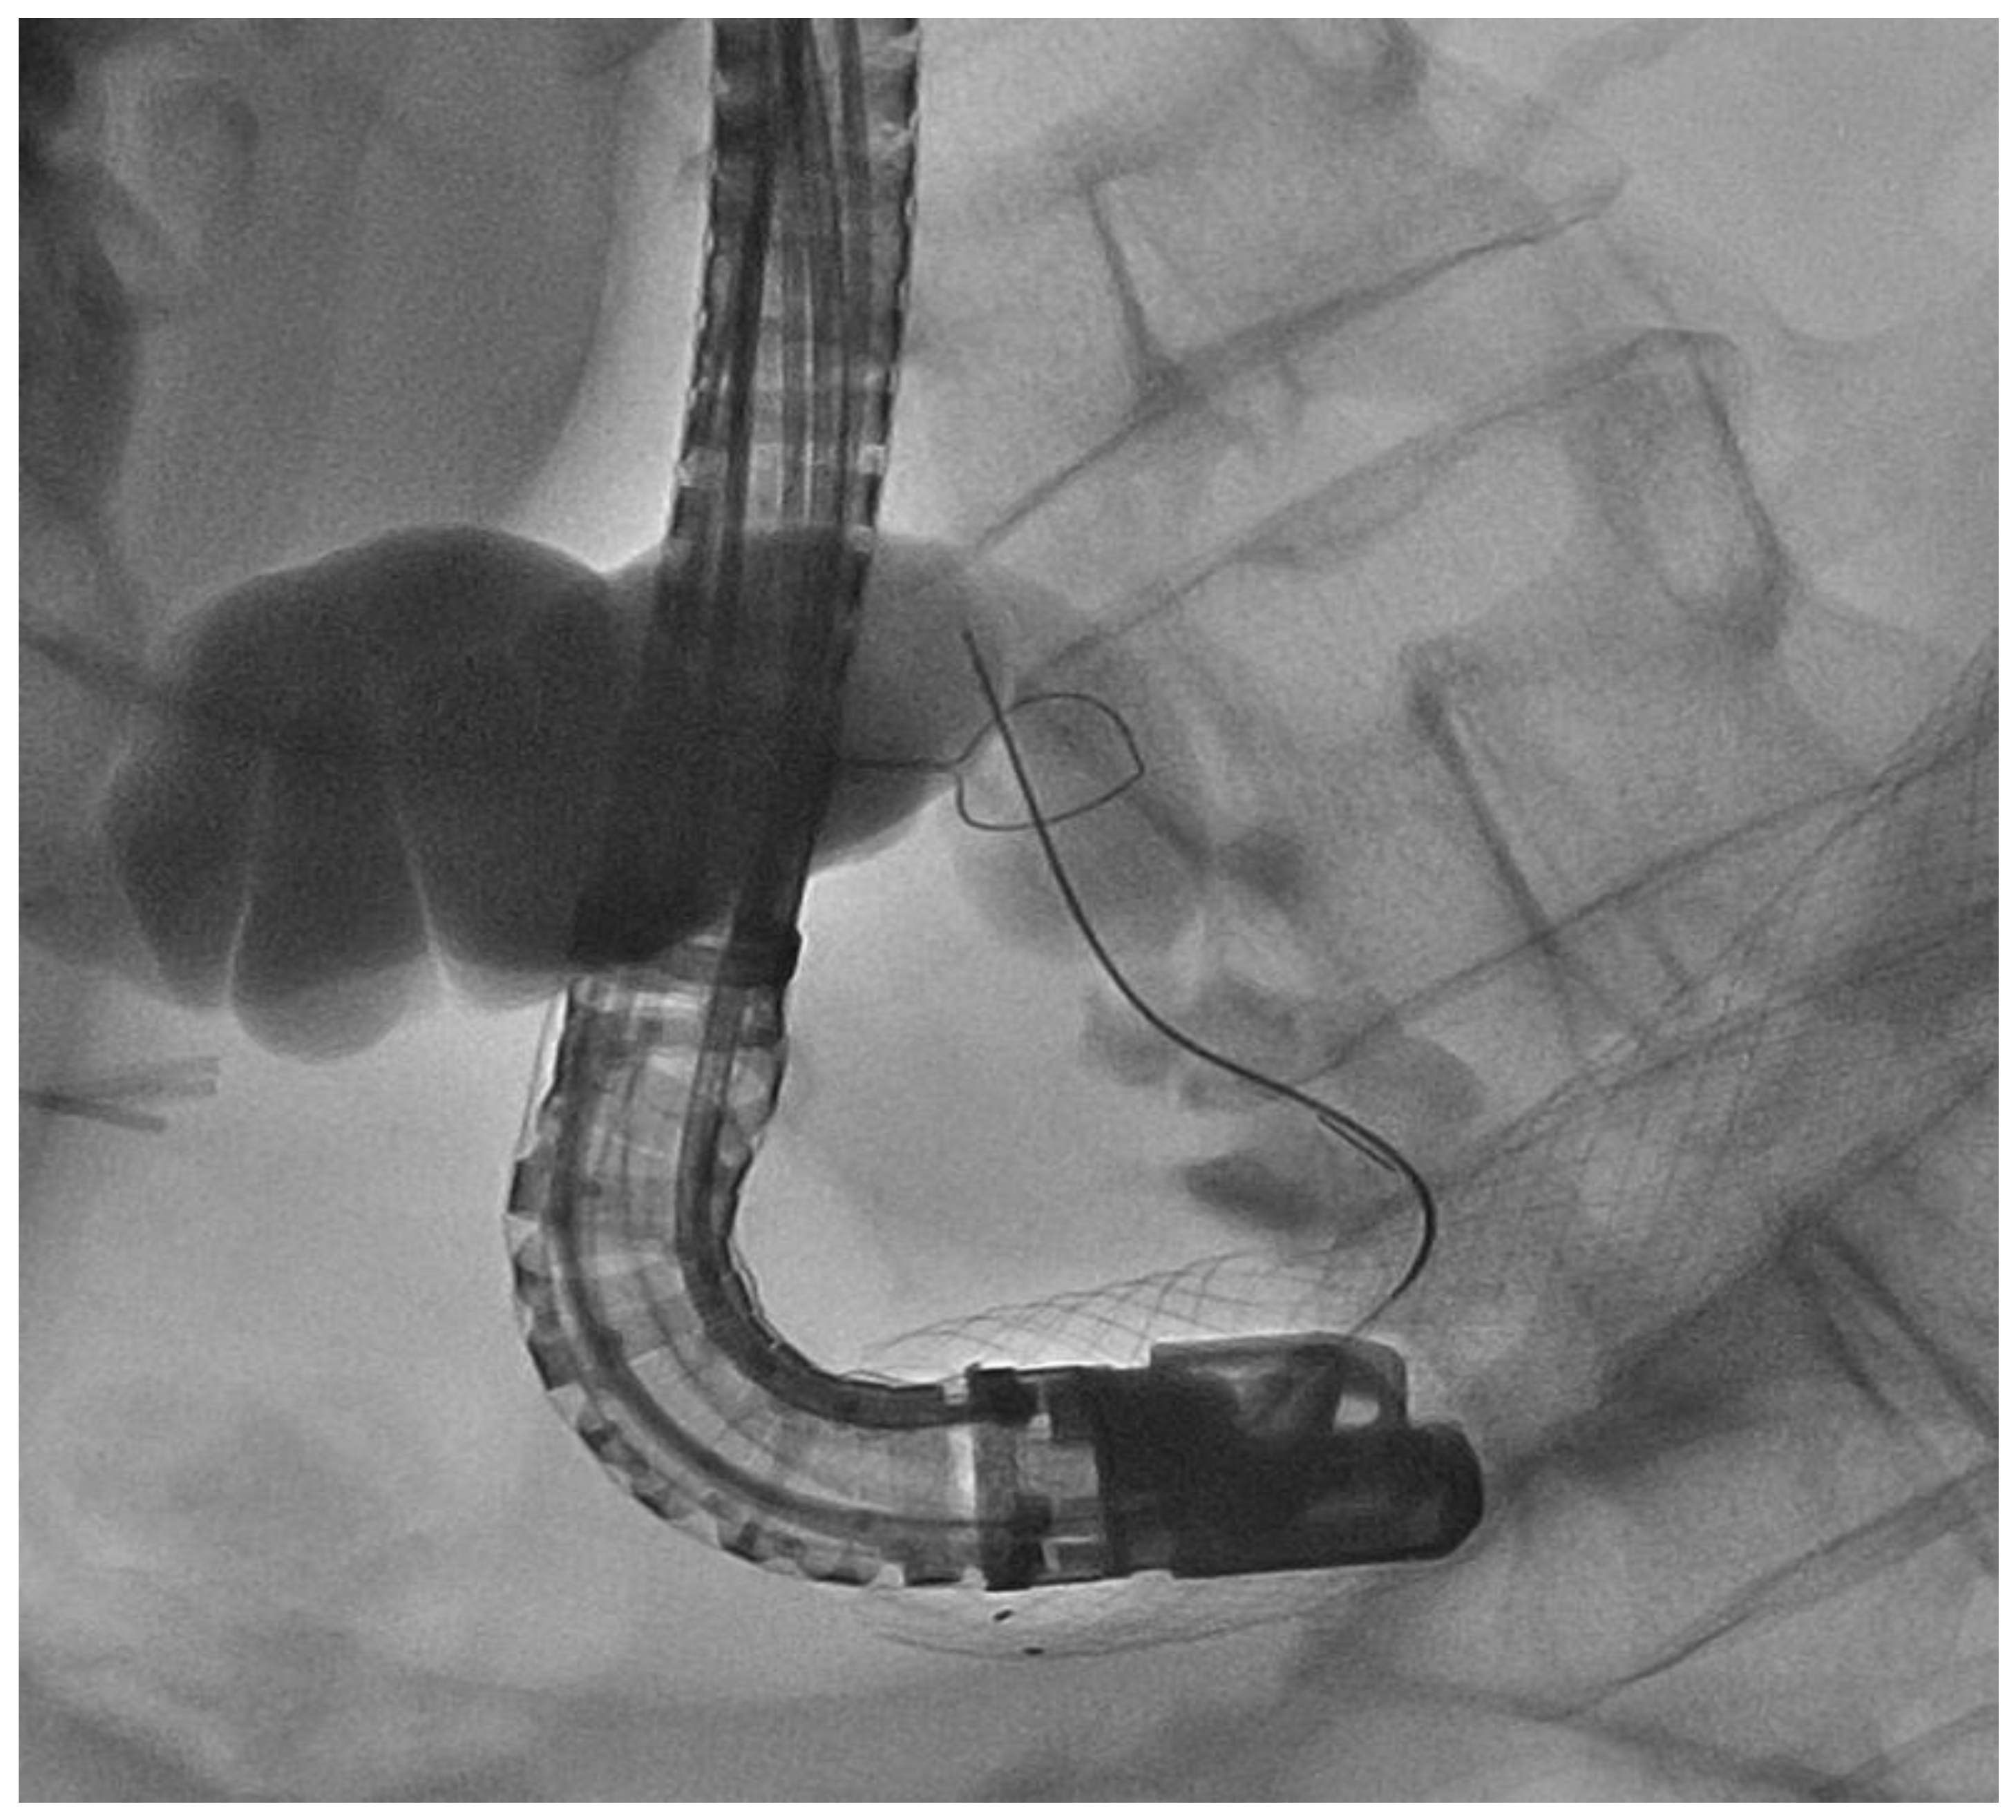

Malignant Gastric Outlet Obstruction Caused by Duodenal Cervix Metastasis in a Young Woman: Rendezvous Technique

2. Case Discussion